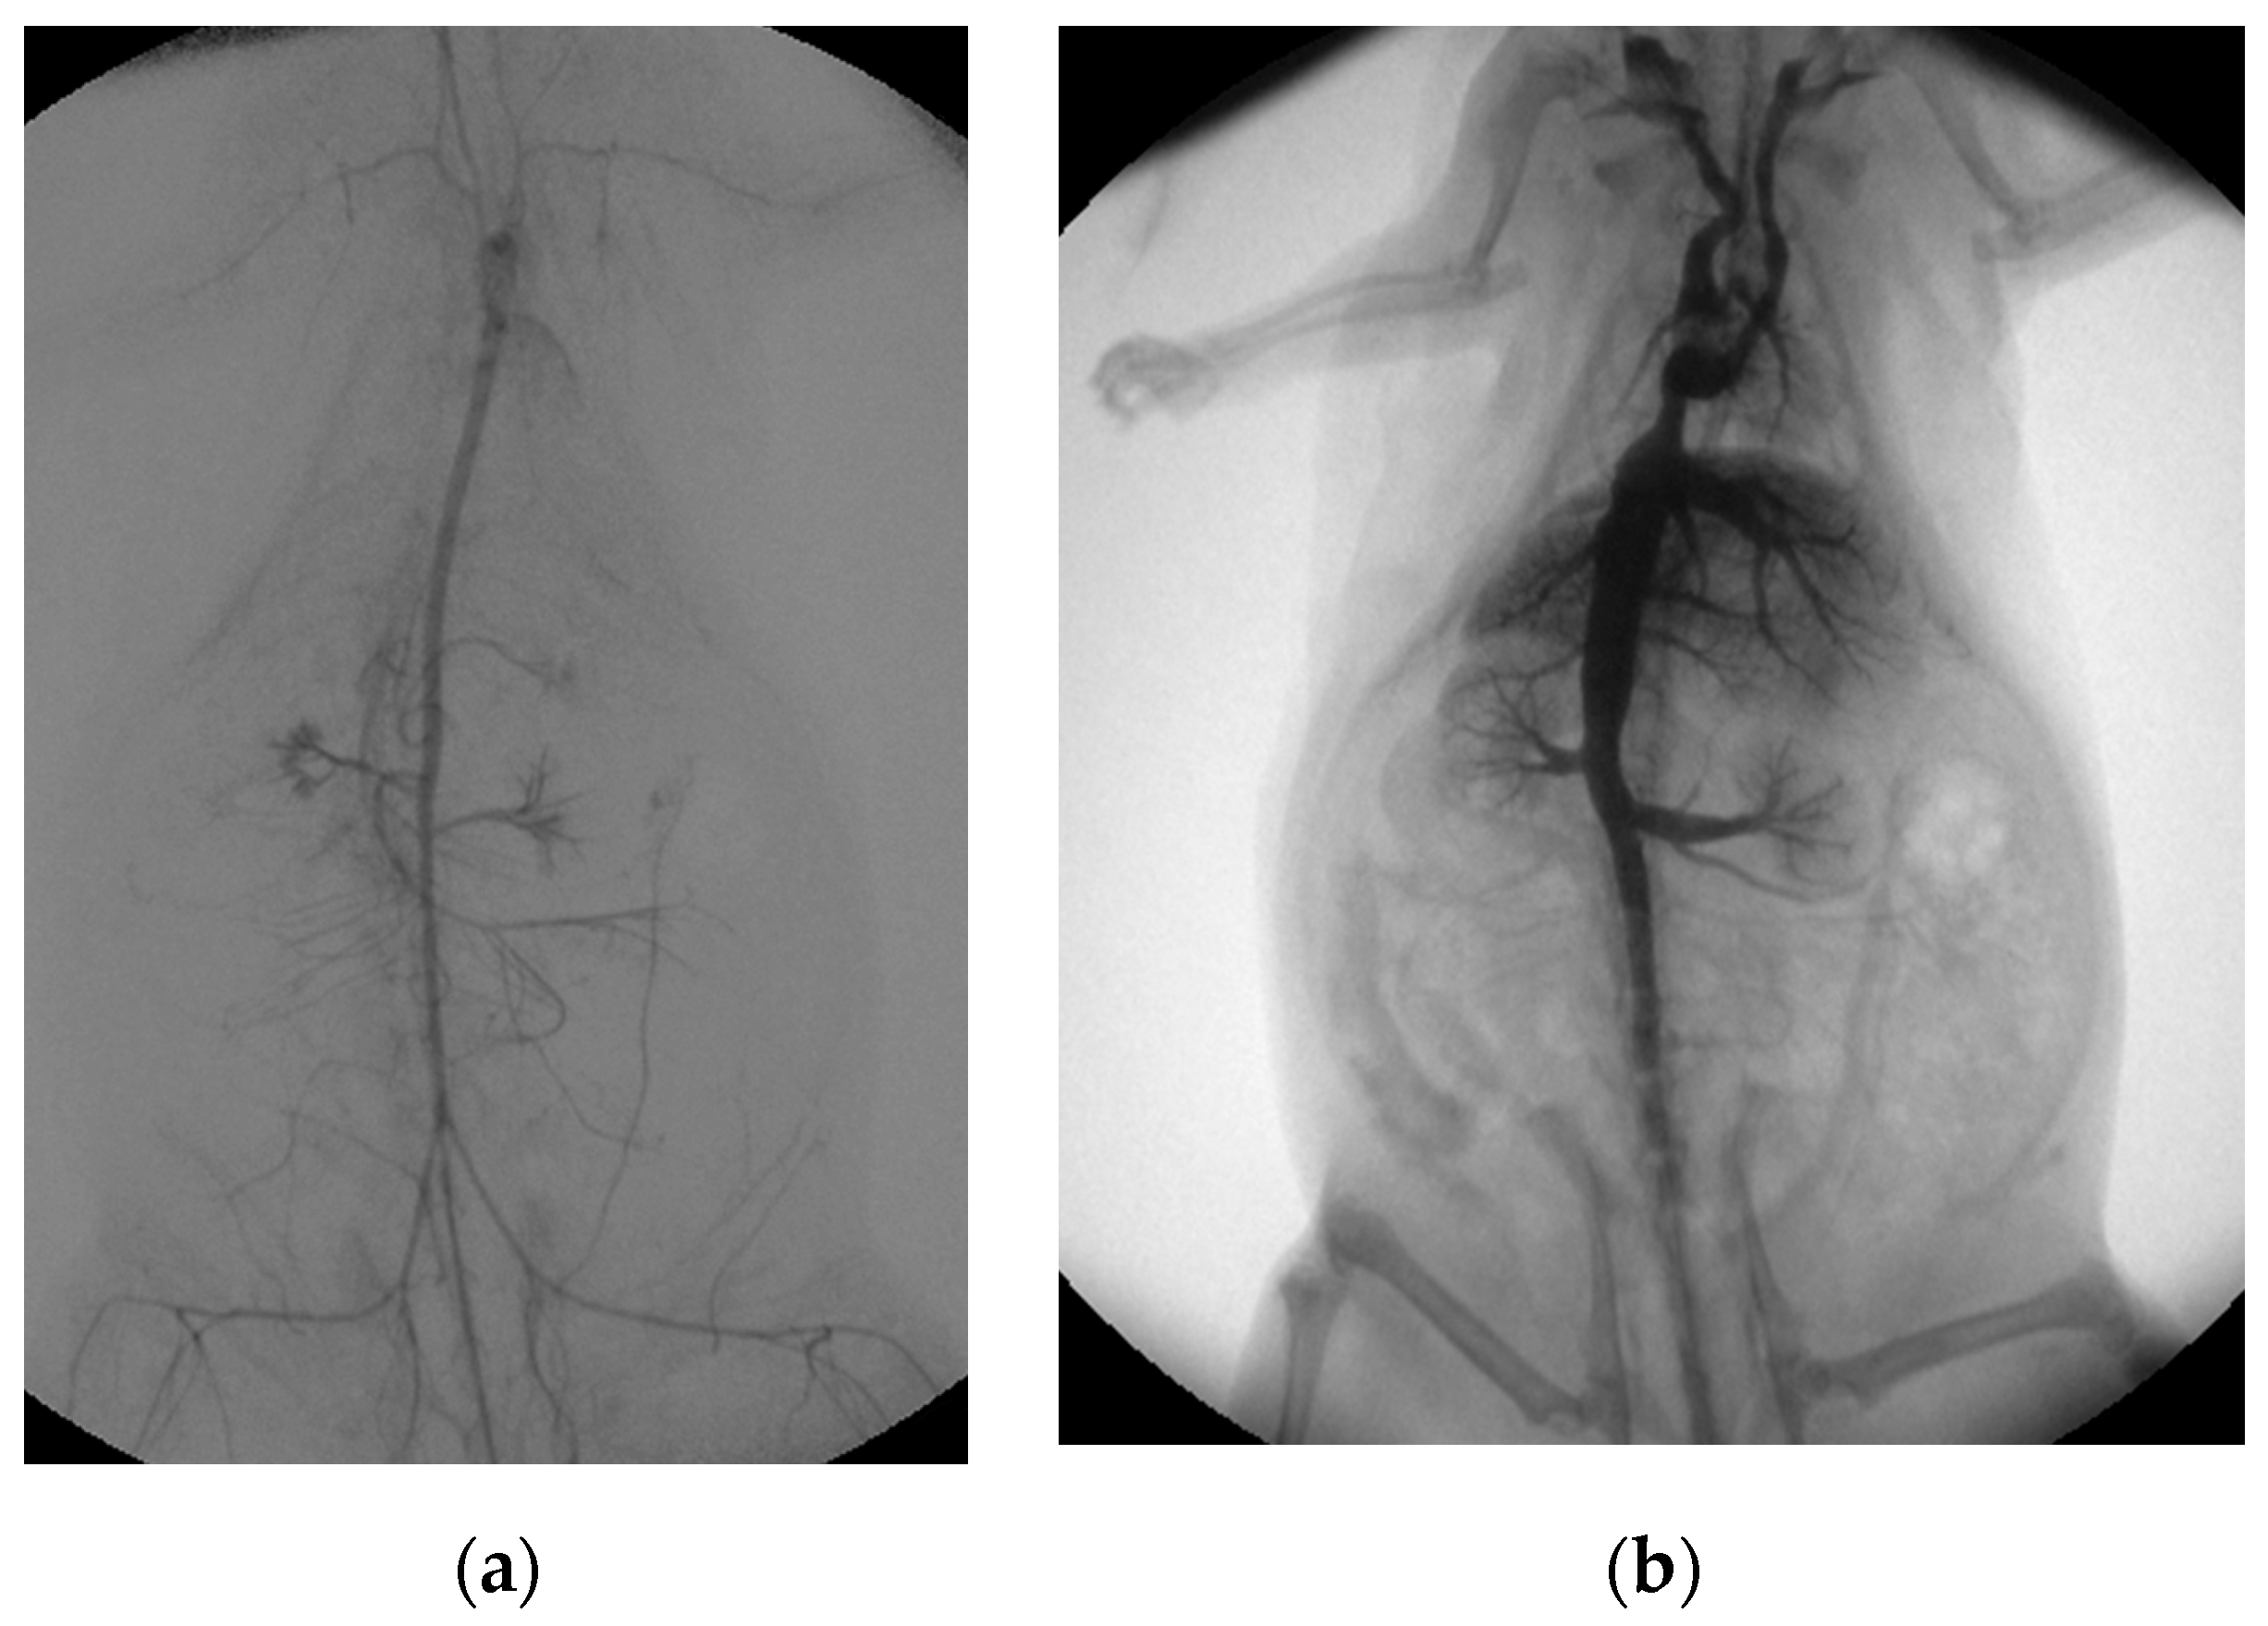

Both the extracorporeal and femoral–arterial blood pressures nearly halved within the first three hours while the speed of the roller pump remained constant (femoral pressure: (0 h) 74 ± 24 mmHg; (1 h) 41 ± 11 mmHg, −45%; (2 h) 38 ± 17 mmHg, −49%; (3 h) 39 ± 13 mmHg, −47%; pre-oxygenator pressure: (0 h) 68 ± 21 mmHg; (1 h) 65 ± 24 mmHg, −4%; (2 h) 56 ± 27 mmHg, −18%; (3 h) 45 ± 11 mmHg, −44%; Supplementary Figure S1). However, a mean femoral–arterial blood pressure of about 40 mmHg was maintained over the entire period in all rat cadavers for organ perfusion (mean pressure: 43 ± 17 mmHg). Organ perfusion was additionally visualized by angiographic imaging. Arterial perfusion was analyzed by native as well as digital subtraction angiography and showed sufficient distribution of contrast medium into the vessels of all major abdominal organs as well as the extremities (Figure 3a; Supplementary Videos S1 and S2). Venous perfusion was visualized by retrograde contrast application and, likewise, showed the perfusion of all major abdominal organs (Figure 3b). The body temperature of the rat cadavers asymptotically approached room temperature (22 °C), which was reached in absence of an external heat supply after about 4 h (Supplementary Figure S1).

Figure 3. Post-mortem ECMO perfusion angiography. (a) shows the angiographic summation image of digital subtraction angiography after arterial contrast agent application. (b) illustrates the fluoroscopic image, with the venous retrograde application of contrast medium into the rat cadaver.